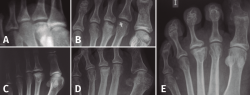

Figura 3. Fases evolutivas de la necrosis. A: fase inicial; B: fase de reparación; C: fase de repercusión articular; D: fase artrósica.

Como en todas las necrosis óseas, la radiología es característica y se corresponde con la fase evolutiva de la necrosis (Figura 3):

- Fase inicial en la que se produce la isquemia con la consiguiente muerte celular. En esta primera fase la radiología es negativa y el diagnóstico se establece con la ayuda de la gammagrafía y la resonancia magnética nuclear (RMN).

- Fase de reparación en la que existe una revascularización alrededor de la zona necrótica: vemos en la cabeza una zona más densa, que corresponde al hueso necrosado, y una zona radiolúcida alrededor de ella, que corresponde a la hiperemia.

- Fase de repercusión articular: el cartílago articular se hunde al fallarle el soporte mecánico del hueso subcondral.

- Fase artrósica en la que se ha producido la desestructuración de la articulación con pérdida del espacio articular y reacción osteofítica, tanto en la cabeza del metatarsiano como en la base de la falange.

Figura 4. Estadios de Smillie. A: estadio I; B: estadio II; C: estadio III; D: estadio IV; E: estadio V.

Basándose en la historia natural de la enfermedad y atendiendo a los cambios radiológicos, Smillie(16) clasifica, con propósito terapéutico, la lesión en 5 estadios (Figura 4):

- Estadio 1: aparece una línea de fractura a través de la epífisis.

- Estadio 2: se produce una depresión central de la cabeza por colapso del hueso subcondral. El espacio articular puede ensancharse.

- Estadio 3: la depresión central hace que se proyecten hacia delante los bordes medial y lateral de la cabeza, manteniéndose intacta la parte plantar.

- Estadio 4: la parte central necrosada de la cabeza puede desprenderse de la parte plantar, formándose un cuerpo libre articular.

- Estadio 5: aplanamiento de la cabeza metatarsal y van apareciendo los cambios degenerativos secundarios.